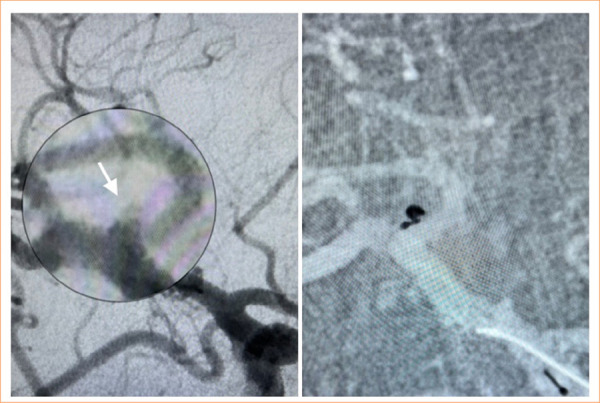

Purpose: To evaluate the angiographic outcomes of the Optima™ coil system in the endovascular treatment of saccular intracranial aneurysms to present real-world experiences.

Methods: The study encompassed patients with both ruptured and unruptured aneurysms who underwent treatment with the Optima™ coil system. A retrospective analysis was conducted to examine patient and aneurysm characteristics, complication rates, and angiographic outcomes.

Results: The total of 326 Optima™ coil implantations was performed in 64 aneurysms, with a mean maximum diameter of 7.49 ± 3.08 mm (range: 2.5-16.5 mm), among 64 patients (37 females and 27 males, mean age: 53.34 ± 14 years old). The average number of implanted coils was 5.06 ± 1.73. The mean packing density was 26.2% (range = 19.2-34.6), observed to be significantly higher in aneurysms with complete occlusion and neck remnants compared to those with a residual dome (p < 0.01). The mean follow-up period was 15.9 ± 8.1 months. One case (1.5%) reported a coil malfunction attributed to coil stretching. The mortality rate was 3.1% (n = 2).

Conclusion: The Optima™ coil system exhibited safety and efficacy in the endovascular treatment of both ruptured and unruptured intracranial aneurysms, demonstrating favorable angiographic outcomes. Nevertheless, further studies are necessary to validate these results over the long term.